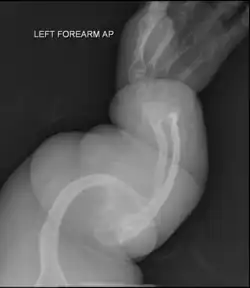

| II | Enfermedad de Vrolik, autosómica recesiva. Se caracteriza por fragilidad ósea extraordinaria, culmina en la muerte en el periodo perinatal o comienzos de la lactancia, huesos largos muy fragmentados (fémur en acordeón), prominencia de hueso parietal y temporal con occipucio colgante y osificación de cráneo retrasada extraordinariamente. |

| V | Autosómica dominante. Es similar al tipo 4. Es más común que se presente en niños que muestran escleras blancas, formación de callo hiperplásico, más común en fémur, tibia y húmero. En radiografías se advierte la formación masiva de callos en forma de mariposa, calcificación de la membrana interósea en el antebrazo y en consecuencia problemas en la pronosupinación de miembros superiores, dislocación de la cabeza radial anterior. |

_of_left_forearm.png)